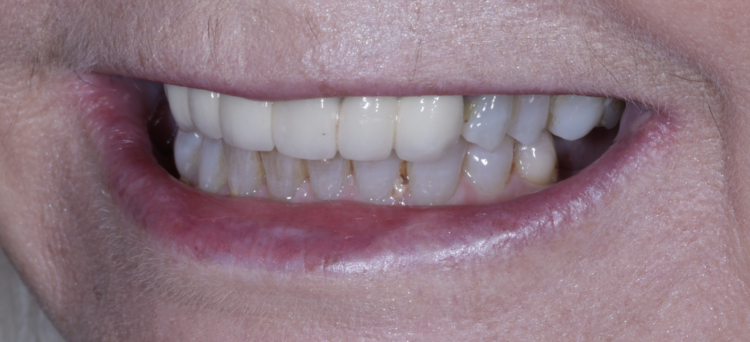

A 61-year-old female patient presented with a failing, upper 3-3, metal ceramic bridge, connected to the canines and lateral incisors on either side. The bridge had failed with caries and core fractures on both abutment teeth on the patient’s left side. As such, the patient was keen to repair or replace the bridge without the use of a removable prosthesis at any point during treatment.

The patient returned to the practice for review two weeks post-surgery and to confirm successful and otherwise uneventful healing. Discomfort was minimal and she reported being very satisfied with the outcome. After a healing period of three months, the patient returned to begin making the final prosthesis. Good soft tissue adaptation was noted around the temporary prosthesis and the buccal contour was successfully maintained.